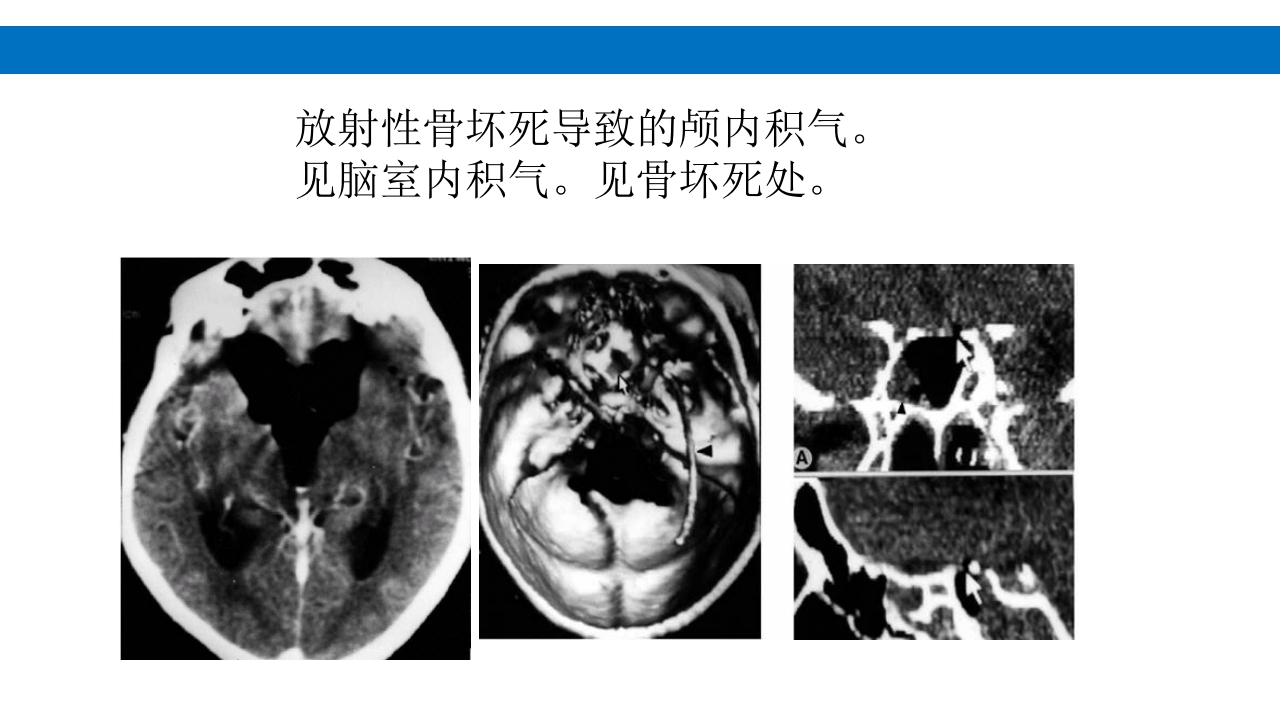

颅脑损伤的并发症及后遗症 讲解人:xxx 20XX年x月x日 1.颅骨骨髓炎 病因:为头皮软组织、中耳、乳突和副鼻窦等处炎性感染而经导 血管侵入颅骨内或颅脑开放伤感染所引起,亦可由菌血症后发生 的细菌栓子由血运转移至颅骨内。 影像学表现: 头部CT: 1.表现为不规则的蜂窝状骨质破坏区,主要位于板障,亦可累 及内外板。 2.破坏区内可见高密度的米粒状细小的高密度死骨。 3.周边可见骨质硬化增生,颅板外无骨膜反应。 4.局部的头皮可见软组织肿胀。 头部MRI: 由于受累部位细胞成分和水量增多,T1WI为低信号, T2WI为高信号,急性期边界不清,慢性期病灶局限, 边界清晰。MRI显示骨质破坏没有CT效果好。 治疗: 除应用抗菌药物控制感染外,当感染局限或已有死骨形成后, 应行手术切除感染...